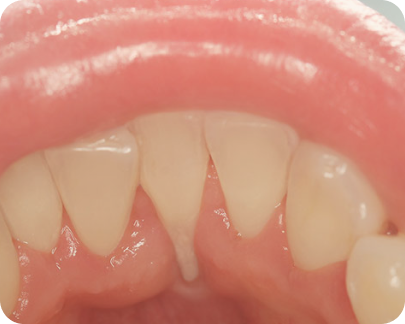

Рецессия десны – состояние, при котором происходит истончение

и убыль мягких тканей, окружающих зубы.

Рецессия десны